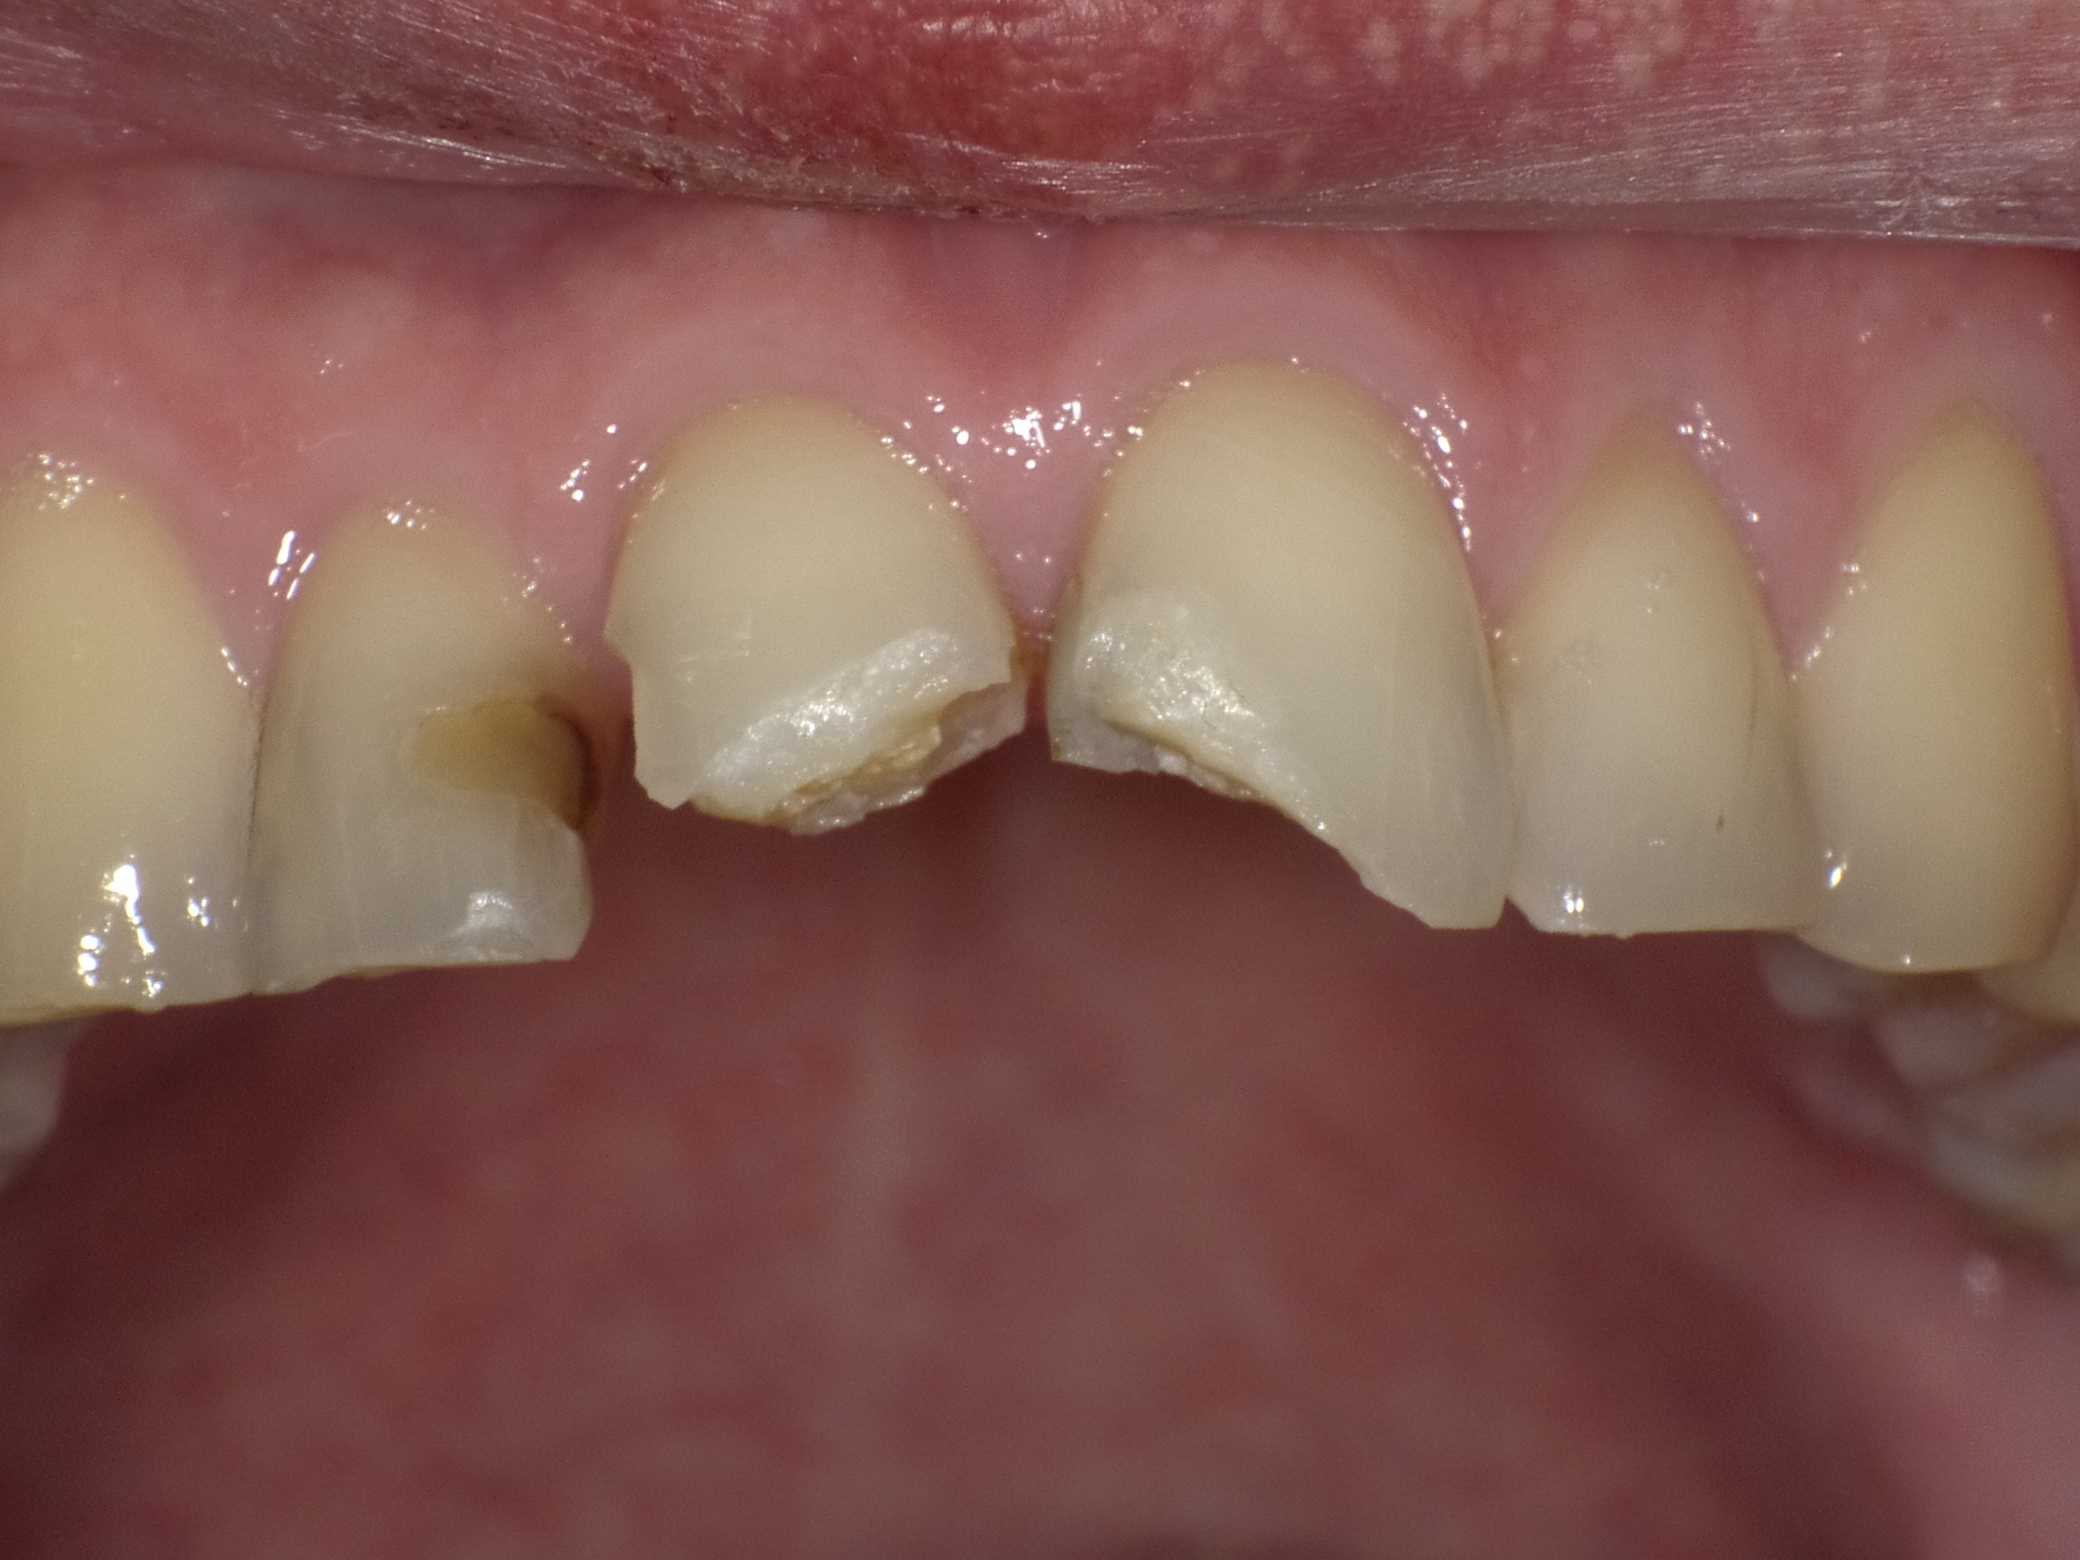

Frontzahnfrakturen nach Unfall

Vorher: Frontzahnfrakturen nach Unfall

Rekonstruktion mit vollkeramischen Kronen

Nachher: Rekonstruktion mit vollkeramischen Kronen